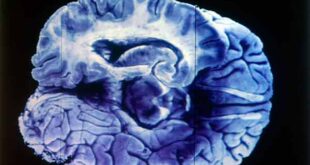

Read More »Alzheimer, enfermedad generada por hasta 20 años de daños en el cerebro

Ciudad de México, 14 de abril de 2024.- El daño molecular cerebral ocasiona el encogimiento y muerte de las neuronas: José Luna Muñoz. Los pacientes no deben ser aislados y tienen que mantener contacto con la familia, resaltó. La enfermedad de Alzheimer se ha incrementado en las últimas décadas al …